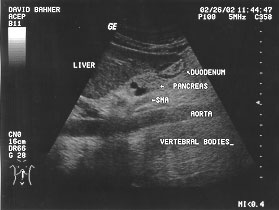

Aorta longitudinal (labeled)